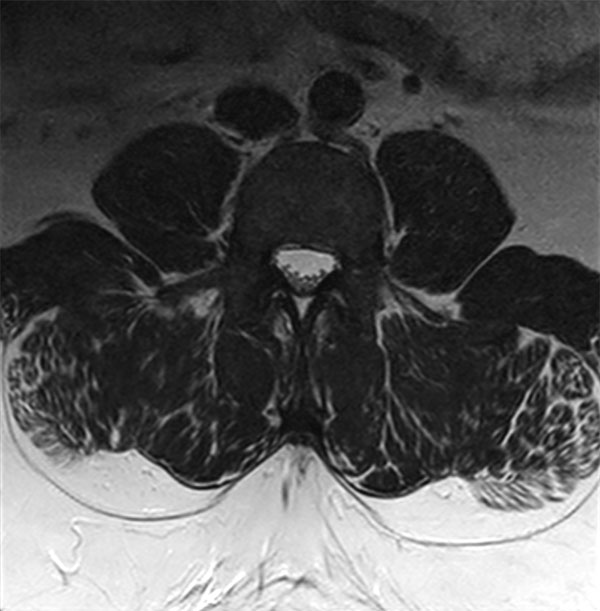

32- year old male patient, 180 kg, with back pain. Was first examined on CT but quality was not sufficient for diagnosis. MRI gave excellent images. Diagnosis: small protrusion of the disc L5/S1, no meningioma.